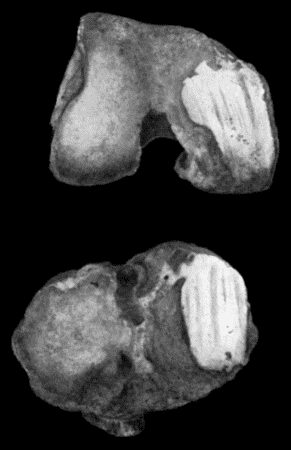

Fig. 1.—Ulcer of back of Hand covered by flap of skin raised from anterior abdominal wall. The lateral edges of the flap are divided after the graft has adhered.

Another modification is to raise the flap but leave it connected at both ends like the piers of a bridge; this method is well suited to defects of skin on the dorsum of the fingers, hand and forearm, the bridge of skin is raised from the abdominal wall and the hand is passed beneath it and securely fixed in position; after an interval of 14 to 21 days, when the flap is assured of its blood supply, the piers of the bridge are divided (Fig. 1). With undermining it is usually easy to bring the edges of the gap in the abdominal wall together, even in children; the skin flap on the dorsum of the hand appears rather thick and prominent—almost like the pad of a boxing-glove—for some time, but the restoration of function in the capacity to flex the fingers is gratifying in the extreme.

Fig. 1.—Ulcer of back of Hand covered by flap of skin raised from anterior abdominal wall. The lateral edges of the flap are divided after the graft has adhered.